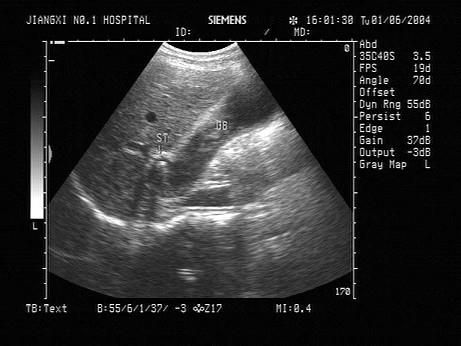

问题 女,34岁,上腹疼痛不适数年,加重二天。声像图如图所示。结合超声声像图,诊断为?(?)

选项 A.胆囊颈部结石并化脓性胆囊炎 B.胆囊颈部息肉 C.胆囊颈部腺瘤 D.胆囊颈部蛔虫 E.胆囊癌

答案 A